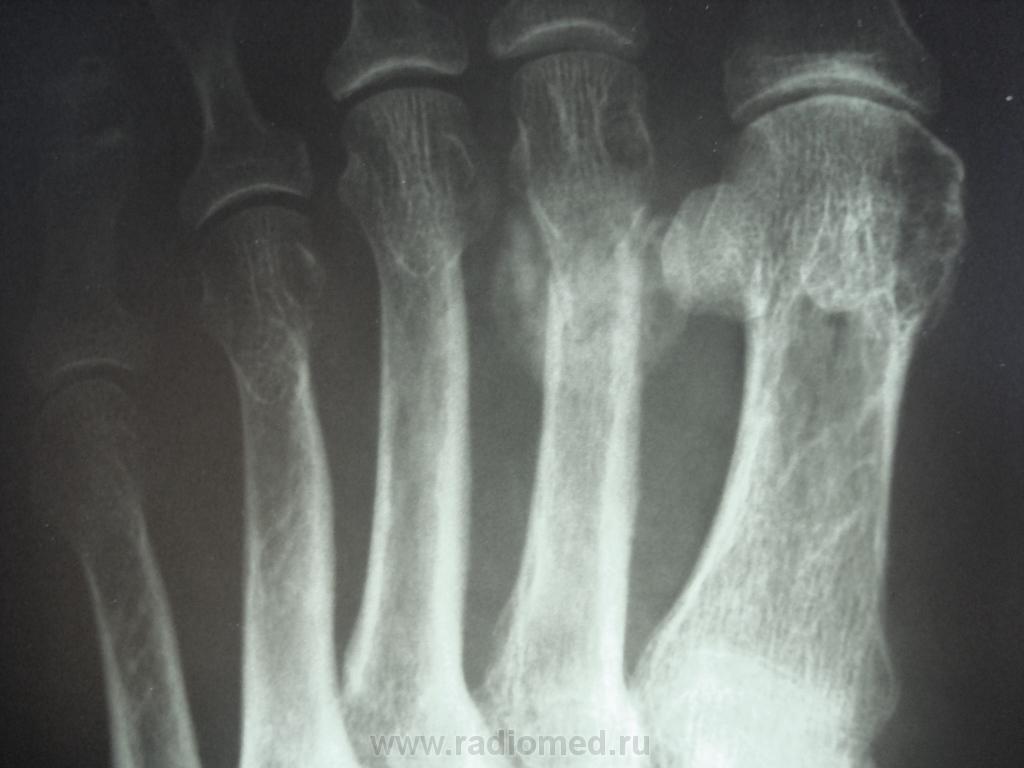

женщина обратилась с жалобами к участковому терапевту на боли во 2 и 3 пальцах правой стопы, предварительный диагноз у них как всегда " артроз", про травму ничего не пишут в амбулаторной карте, как внешне выглядит стопа тоже не описывают. Может ли это быть патологическим переломом????

Перелом по типу маршевого, но так как на фоне минералопении - это ближе к Лоозера, чем Дойчлендера...

А меня что-то смущает и участок, помеченный желтыми стрелками.

Меня не смущает: остеопороз, верхний край участка - проекционное наложение сесамовидной кости, нижний - линейное уплотнение структуры по типу стрессорного перелома, из той же серии лоозеровских зон.

Боюсь прослыть упрямым ... Но все-таки... Дружный DS б-ни Дойчлендера выставлен только на основании утверждения, что травмы не было. Я тут "посоветовался" с С.А.Рейнбергом. Он утверждает, что отличительной особенностью полоски просветления при б.Д. является ее ровность, прямолинейность. При переломах полоска зигзагообразная, что мы и имеем. На фоне остеопении больная могла просто наступить на камень и этого не заметить. Вот вам и перелом.

На рентгенограммах выявляется локальная периостальная реакция в виде одно- или многослойного периостоза. Соответственно ему в костномозговом канале появляется склероз, сужающий просвет канала. В кортикальном слое и среди склероза видна полоска просветления, чаще имеющая клиновидную форму- собственно « ползучий » перелом. При продолжении действии нагрузки он постепенно увеличивается. Однако если травмирующий фактор прекращает свое действие, достаточно быстро восстанавливается нормальная структура кости.